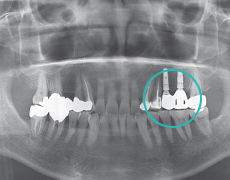

1期手术(植入人工牙根)将种植牙植入到适当的位置。

2期手术(骨结合及连接基台)将种植牙露出并连接基台。